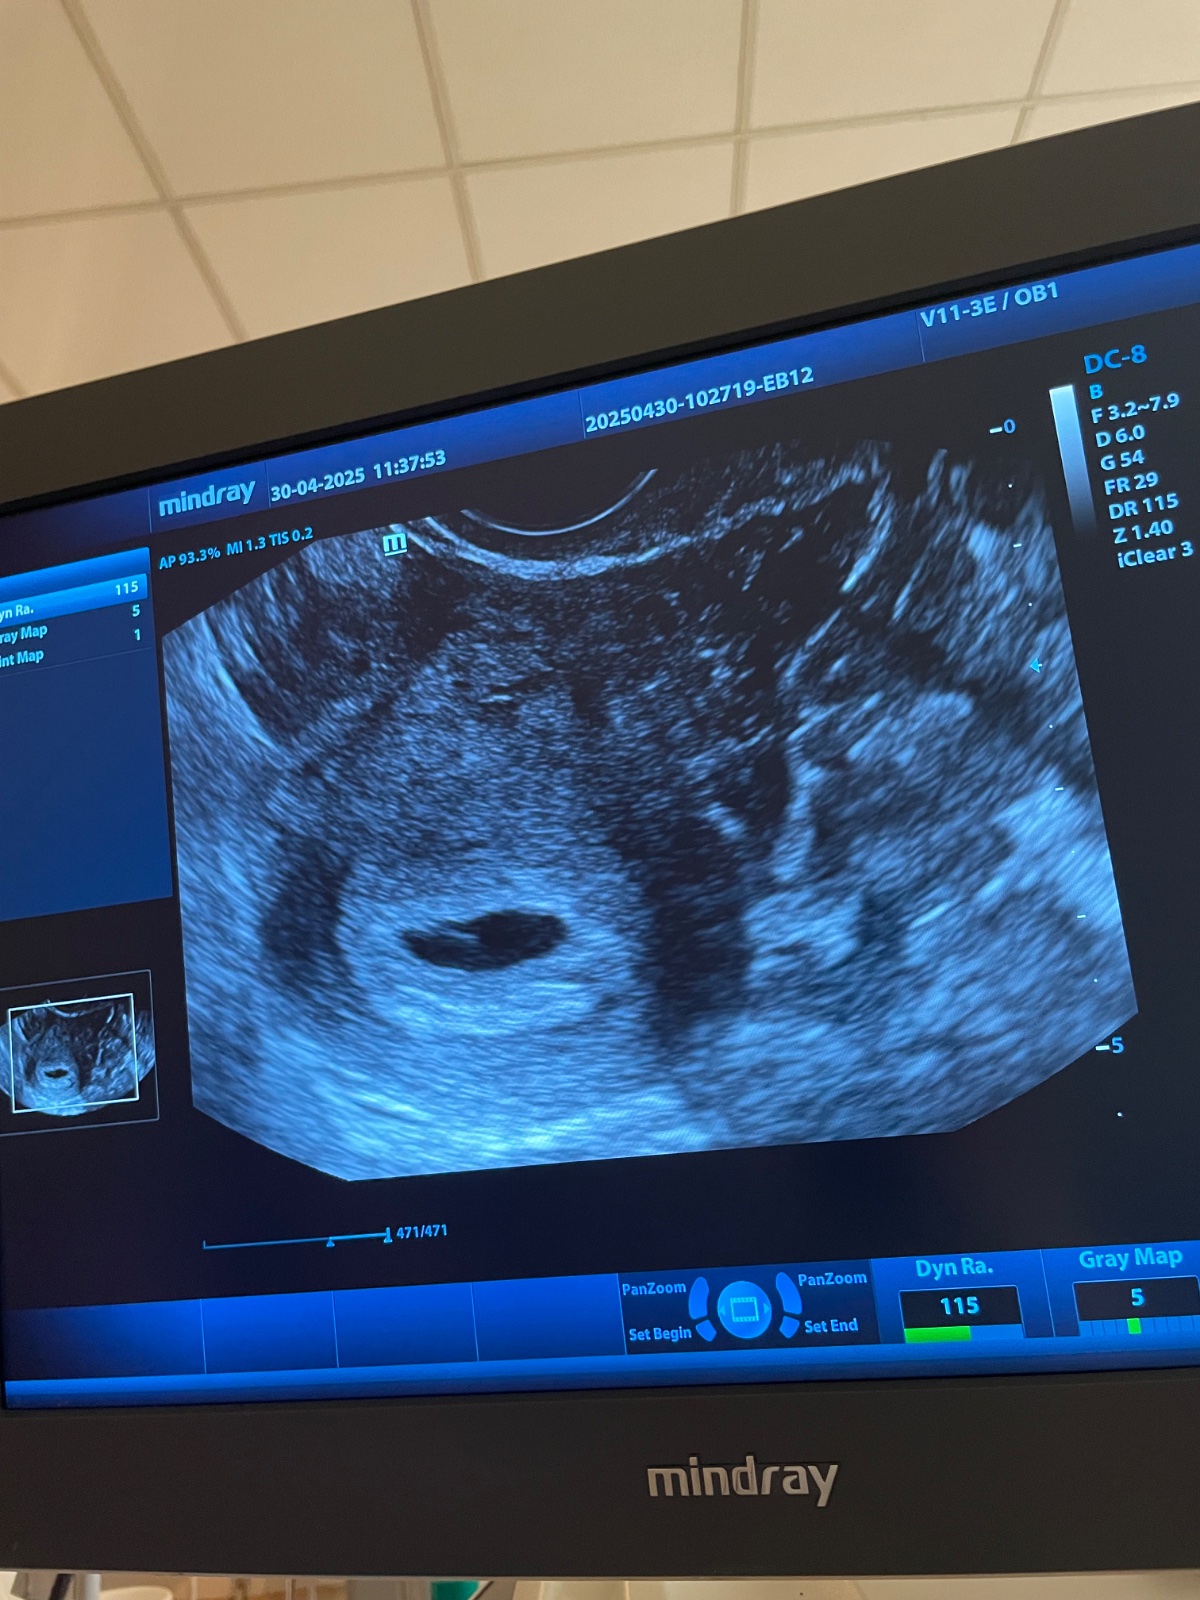

Žienky, snáď som označila všetky 🙂... Už po kontrole a je tam embryjko s akciou srdiečka, podľa ms som 6+6tt a o týždeň mám kontrolu, či rastie ako má 🙂

Inak ja som dnes bola na kontrole som 5+4 - 5+5 a že by tam už zltkovy vak malo byt vidno. Ale zatiaľ nestresoval a objednal ma o týždeň. Že tam vidi tu embryonálnu štruktúru. Bože držte palce. 🥹

@zanzilady teraz som si pozrela svoje poznámky zo začiatku tehotenstva...11.4.2024 som mala hcg 15320...o ďalších päť dní na to,16.4.2024 som bola na pohotovosti lebo som mala tlaky v podbrušku...hcg som musela mať už veľmi vysoké a môj ultrazvuk vyzeral veľmi podobne ako ten tvoj...bola som podľa apky 6+1tt. ...a v správe mi dr.písal že embryonálny základ toho času nevyzualizujem...vravel že budeme čakať...o ďalší týždeň na to som šla k mojej dr.na kontrolu...bola som 7+0tt. ...robila mi usg zo spodu a na obrazovke sme videli iba gestačný vak...krvy by sa mi nikto nedorezal...moja dr.napriek tomu že niesom z tých štíhlych báb vravela že ešte mi skúsi spraviť sono cez bruško a tam sa objavil prcek v celej svojej kráse aj z už bijúcim srdiečkom...dodnes nechápem ako mohol byť tak schovaný že to vaginálne sono ho vôbec neukázalo keď práve to sa na tak včasné určenie tehotenstva používa...

@majulka098 to je krásna fotka...husiu kožu mám na celom tele a slzy v očiach ❤️🙏....tak veľmi sa teším...krásna správa ❤️❤️❤️❤️❤️❤️❤️